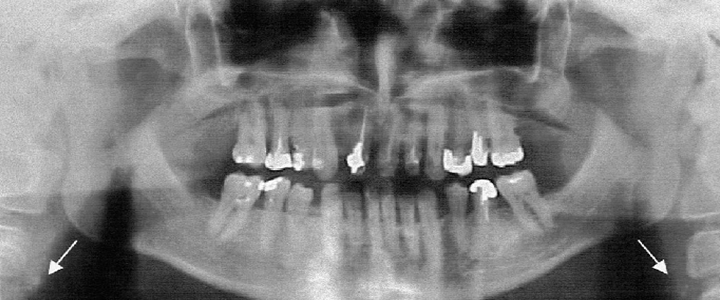

The digital radiograph x-ray at our Gainesville Dental Arts offers superior resolution with less radiation exposure and is an excellent new way to help diagnose possible oral problems. The digital radiograph not only emits significantly less amount of radiation associated with traditional x-rays, but is also much less time consuming.

Using a sensor that is placed in your mouth in the correct position, the pictures are taken and immediately sent to our computer. We can then review the information with you right from the computer screen.